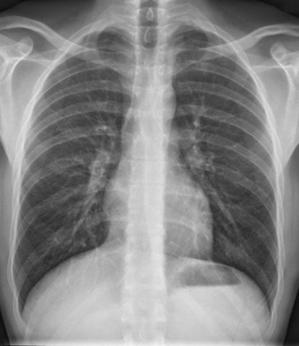

Röntgen cihazları X ışını kullanan ve bu nedenle iyonizan radyasyon oluşturan cihazlardır. X ışını dokulardan geçer ve analog film ya da dijital plakalar üzerinde görüntü oluşmasına yol açar. Röntgen incelemesi başta kemik ve akciğer yapılarını değerlendirmek için kullanılmakla birlikte vücudumuzun birçok yerinde tanısal açıdan kullanılır.

Bu tetkik iyonizan radyasyona yol açtığı için tekrarlayan incelemelerden kaçınılmalı ve belli aralıklarla yapılmalıdır. Gelişen radyoloji teknolojisi ile bu cihazlarda doz kontrollü incelemeler yapılabilir hale gelmiştir. Bu şekilde hastanın vücut tipine göre doz otomatik olarak ayarlanır ve hastanın fazla radyasyon dozu alması önlenir.